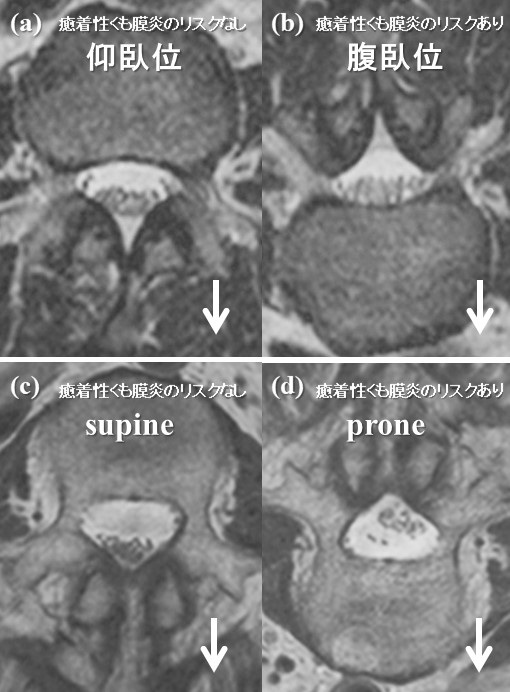

腰部癒着性くも膜炎がある人とない人との神経の動きを比較したMRI検査の図

腰部癒着性くも膜炎がある患者さんとない患者さんに、MRI検査を行いました。MRI検査は通常、仰向けでしか撮影しませんが、うつ伏せでも撮影を行い、背骨の中にある神経が通るトンネル内で重力に応じた神経の動きを可視化しました。(a)と(b)は癒着性くも膜炎がない患者さんの画像で、(c)と(d)は腰部癒着性くも膜炎がある患者さんです。また(a)と(c)は仰向けで、(b)と(d)はうつ伏せで撮影したものです。白い矢印は重力の方向を示しています。腰部癒着性くも膜炎の患者さんでは、重力によって神経が腹側に降りてこず、神経同士と神経とトンネル(硬膜)壁がひっついている(癒着している)ことが分かります。